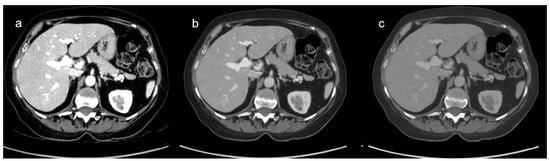

3.3. Comparison of DECT and SECT Results

3.3.1. DECT and SECT Comparison: Qualitative Results

3.3.2. DECT and SECT Comparison: Quantitative Analysis Results